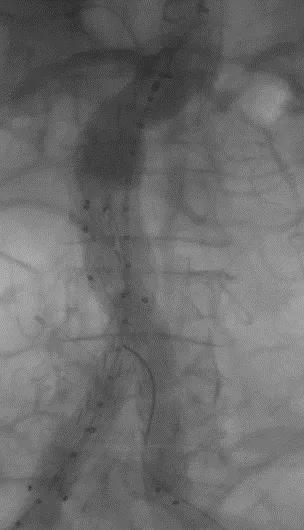

手术顺利,无内漏,持续时间1小时10分钟。术后CTA检查,支架形态良好,无内漏。详见下图:

术前影像

术中影像

出院前影像